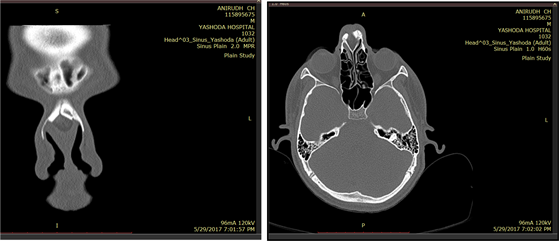

We ordered a CT scan of the nose and paranasal sinuses [Figure 1] which showed a swelling on the dorsum of the nose with splaying of the nasal bones. Also a MRI with contrast [Figure 2] was done which showed mixed signal intensity mass lesion which approximately measures 2.69 × 1.50 cms in the anterior nasal cavity within the anterior septum, associated with sinus tract extending superiorly to the foramen caecum with no intracranial extension.

Figure 1. Computed tomography of nose and paranasal sinuses showed swelling over the dorsum of the nose with splaying of nasal bones.